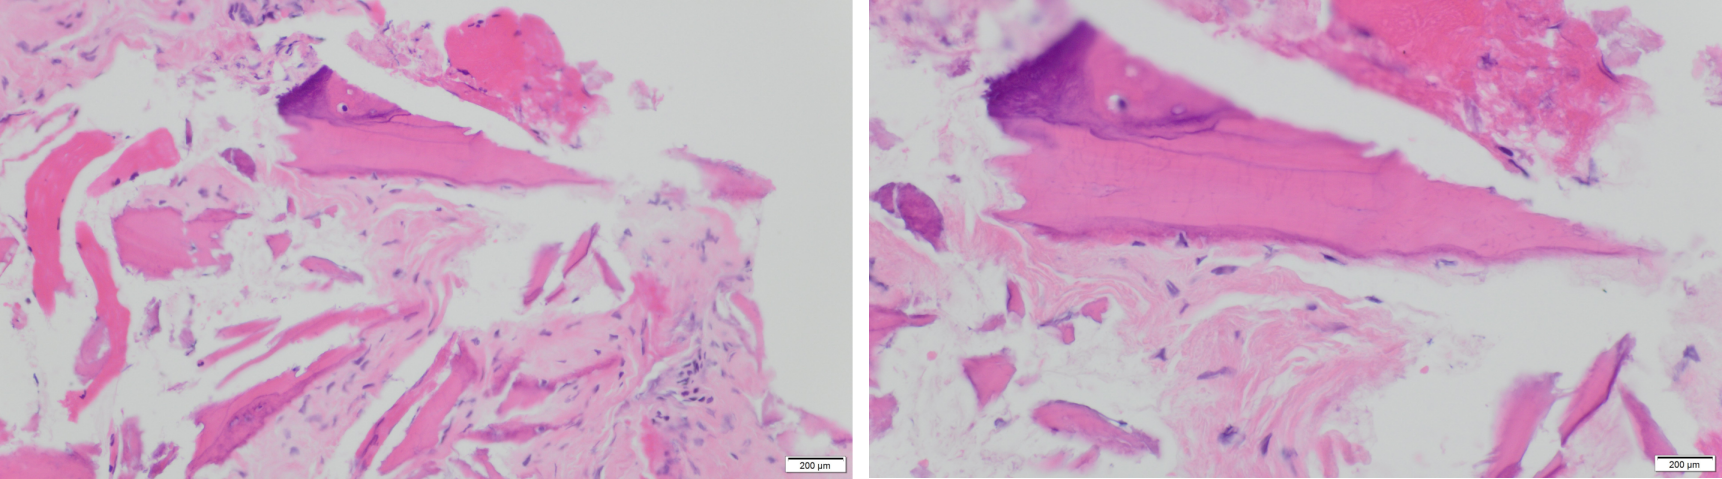

The surgical specimen was fixed in neutral-buffered formalin and sent to the pathological anatomy department of our hospital, where it was decalcified in formic acid, embedded in paraffin, sectioned at 4-µm thickness, and stained with hematoxylin-eosin. The histopathological analysis of the decalcified samples showed areas of bone necrosis with inflammatory cell infiltration, several basophilic bacterial colonies, empty Haversian canals without residual osteocytes/osteoblasts, and fewer Haversian blood vessels, thus confirming the clinical diagnosis of MRONJ (Figure 7 [Fig. 7]).

Figure 7: Histopathological analysis of the decalcified samples stained with hematoxylin-eosin shows areas of bone necrosis with inflammatory cell infiltration and several basophilic bacterial colonies, empty Haversian canals without residual osteocytes/osteoblasts, and reduction of Haversian blood vessels, thus confirming the clinical diagnosis of MRONJ (left: 200× magnification, right: 400× magnification). Areas of remaining vital alveolar bone are also shown.